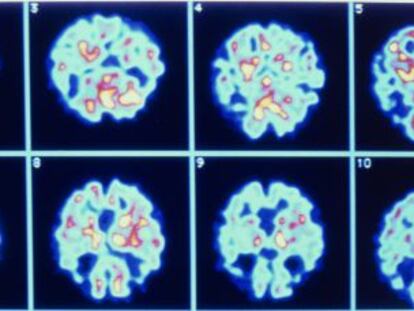

Un nuevo método indica si aparecerá la enfermedad en un año con un simple análisis de sangre El grado de fiabilidad de la prueba desarrollada por investigadores británicos es del 87%

El ensayo se basa en la existencia de 10 lípidos en sangre